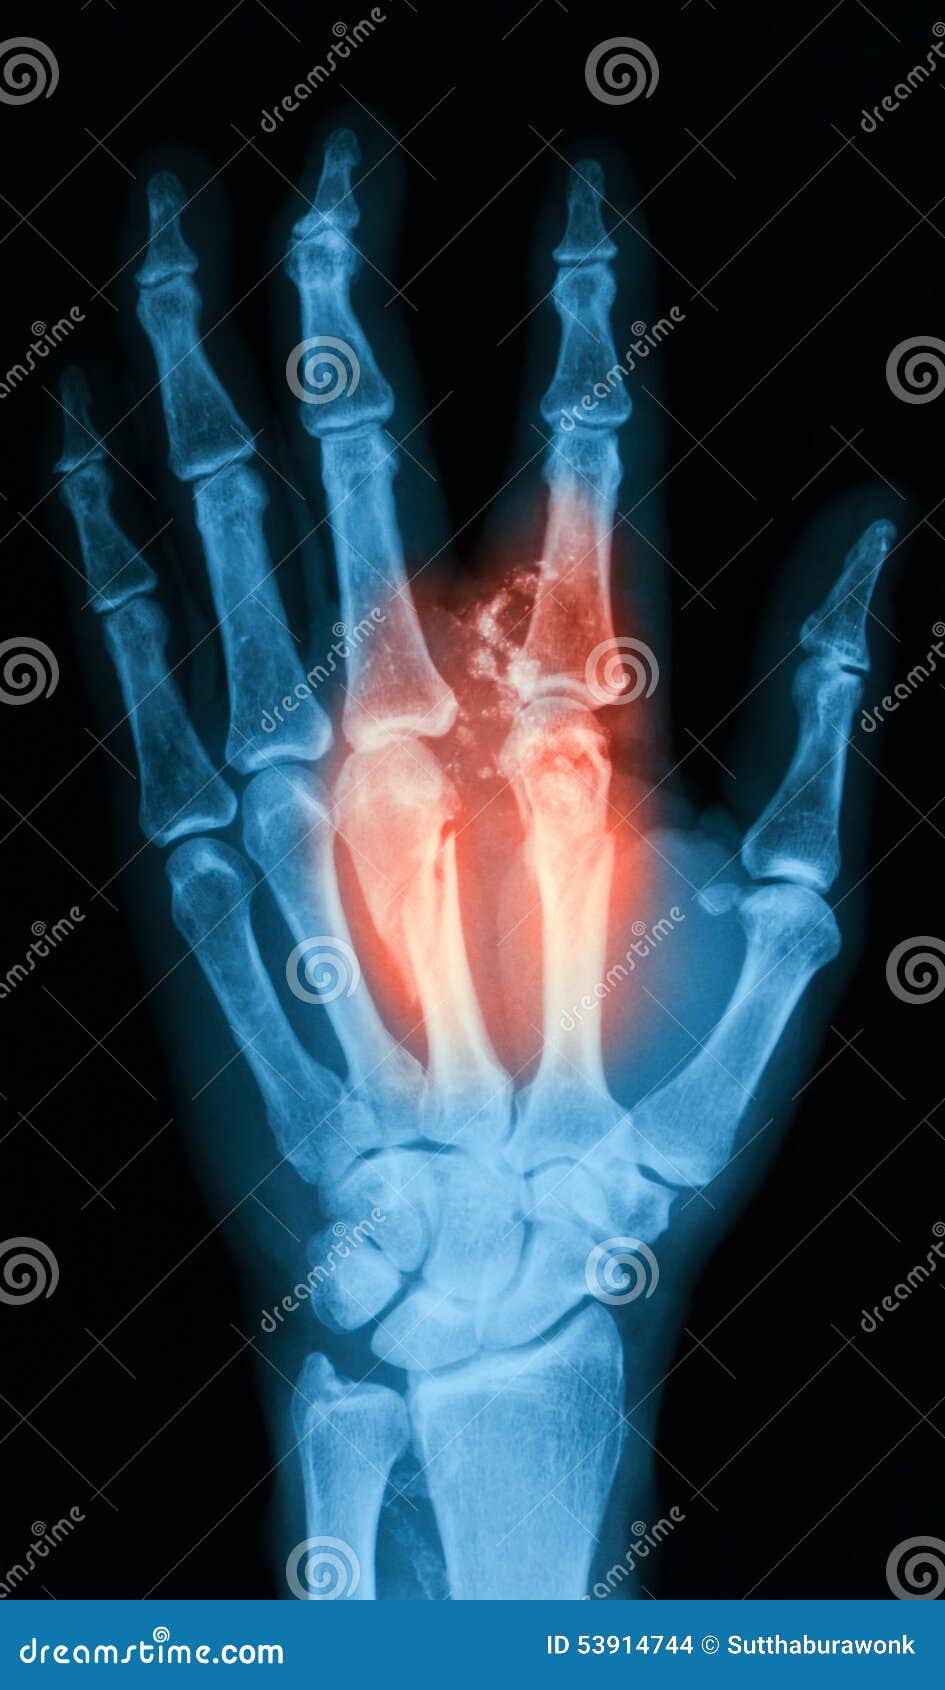

Xray Image of Broken Hand, AP View. Stock Photo Image of medical Fracture X Ray Hand Diagnosis is made by orthogonal radiographs the. Metacarpal fractures are the most common hand injury and are divided into fractures of the head, neck, or shaft. Your doctor will also look for injuries to other nearby structures. They are in pain and have a reduced range of motion. This includes the small bones of the fingers (phalanges) and the long. Fracture X Ray Hand.

Film Xray of Hand Fracture Show Fracture Metacarpal Bone Stock Image Fracture X Ray Hand Metacarpal fractures are the most common hand injury and are divided into fractures of the head, neck, or shaft. Diagnosis is made by orthogonal radiographs the. Stable nondisplaced fracture (majority of fractures) if patient has normal xrays but there is a high level of suspicion can. Your doctor will also look for injuries to other nearby structures. Primary care of. Fracture X Ray Hand.